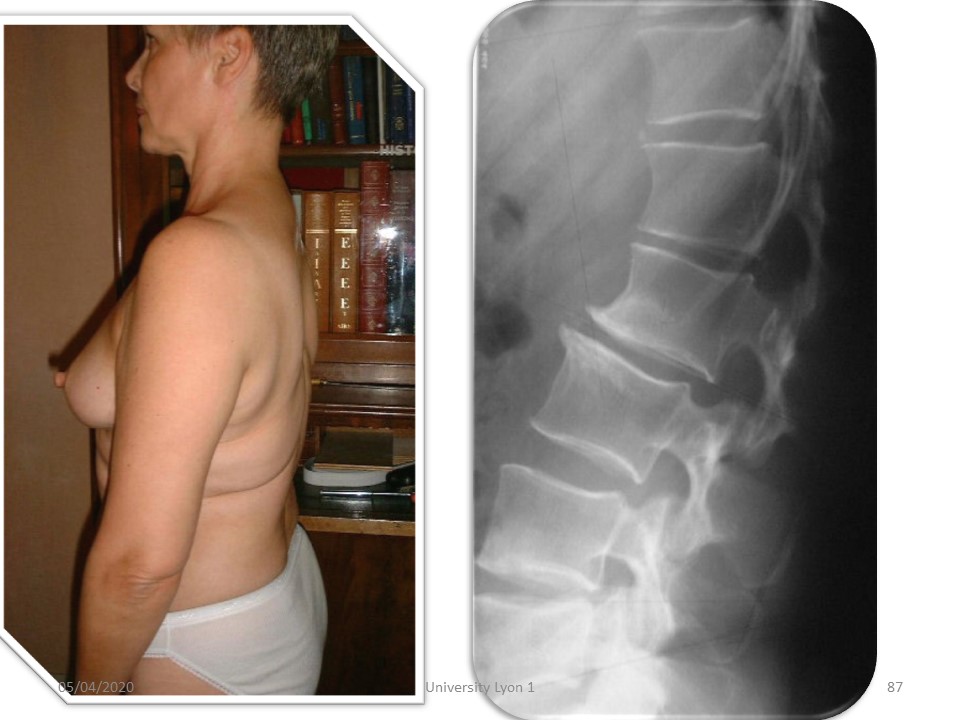

Scheuermann stage 2 in this patient with wedging of more than 7° of the vertebral body (physiological limit). |

|